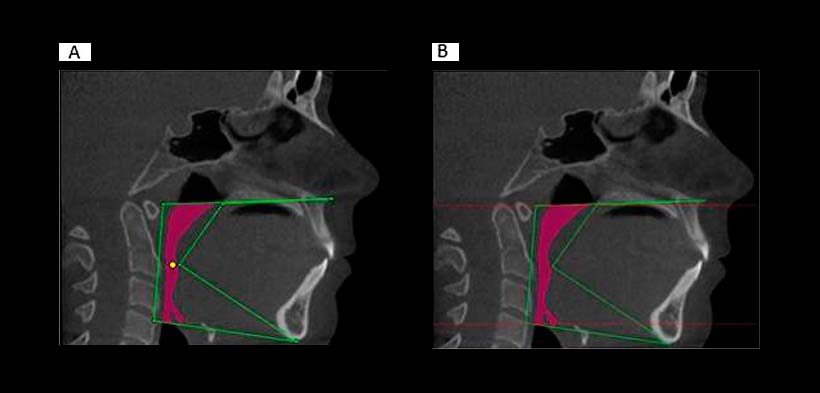

-LIMITE SUPERIOR: línea que pasa a través del plano palatino (espina nasal anterior a posterior espina nasal) que se extiende a la pared posterior de la faringe)

-LIMITE INFERIOR: línea que pasa por el borde anterosuperior del vertebra cervical C4 al mentón.

-LIMITE ANTERIOR: línea que pasa por el paladar blando a mentón.

-LIMITE POSTERIOR Y LATERAL: Las paredes de la faringe respectivamente.

El volumen de las vías respiratorias (mm3) se calculó automáticamente por el software dentro de los márgenes definidos anteriormente.

Fig. 2. Evaluación de la vía aérea superior. (a) Los márgenes para la delimitación de la vía aérea superior. Las líneas verdes indican los márgenes utilizados para delinear la vía aérea. El punto amarillo representa el punto de inicio. (b) Los márgenes de sección transversal mínima. Las líneas rojas indican los límites superior e inferior utilizados para medir el área de sección transversal mínima.